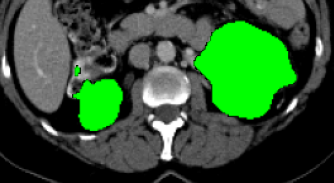

Current research on deep learning for medical image segmentation exposes their limitations in learning either global semantic information or local contextual information. To tackle these issues, a novel network named SegTransVAE is proposed in this paper. SegTransVAE is built upon encoder-decoder architecture, exploiting transformer with the variational autoencoder (VAE) branch to the network to reconstruct the input images jointly with segmentation. To the best of our knowledge, this is the first method combining the success of CNN, transformer, and VAE. Evaluation on various recently introduced datasets shows that SegTransVAE outperforms previous methods in Dice Score and $95\%$-Haudorff Distance while having comparable inference time to a simple CNN-based architecture network. The source code is available at: https://github.com/itruonghai/SegTransVAE.